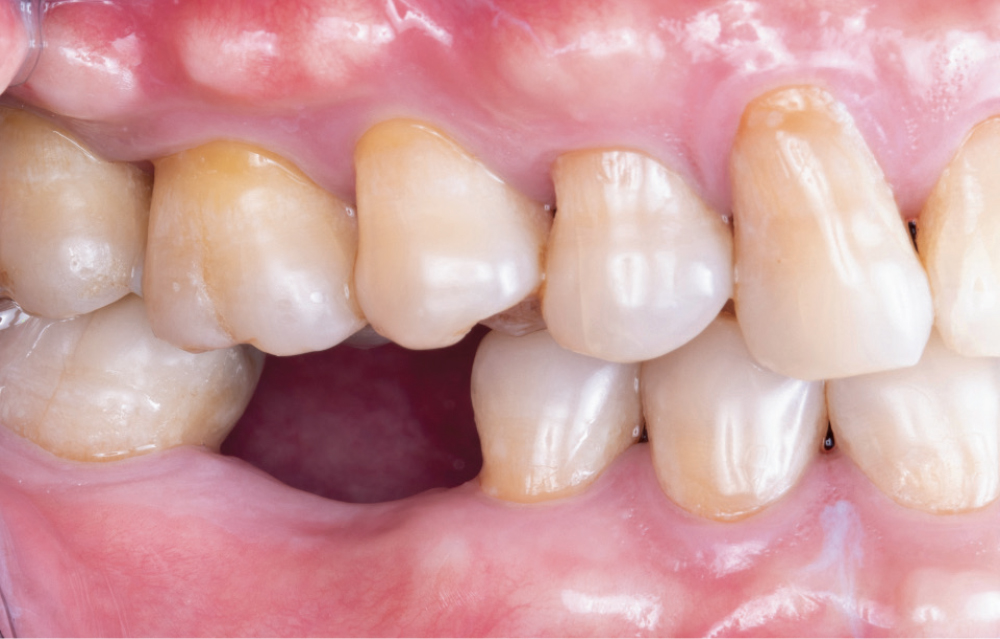

Ted Vo, a dental technician in the Glidewell implant department, came to our clinic because he had been missing tooth #30 for several years. He reported difficulty eating and was self-conscious about the edentulous space that sometimes showed when talking and laughing. Except for an occlusal amalgam restoration on #31, the adjacent teeth were healthy. My treatment plan called for an implant and a BruxZir® Esthetic Zirconia screw-retained crown, which the patient accepted.

Before Restoration

After Restoration

Figures 18a, 18b: The final restoration seated perfectly without the need for any adjustment. The custom healing abutment created an emergence profile that allowed the final restoration to blend seamlessly with the adjacent teeth and appear to emerge from the tissue like a natural tooth. The result blends well with the adjacent dentition, restoring both function and esthetics.